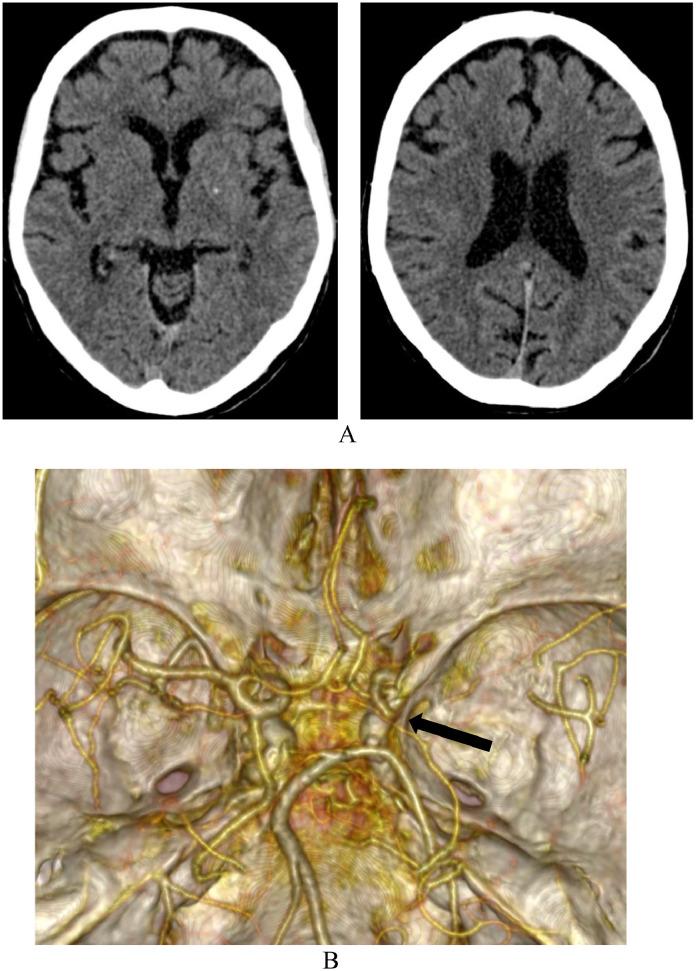

This case report presents a clinical case of management of a patient with concomitant ischemic stroke and acute arterial ischemia of the right upper limb. Emergency thrombaspiration from the middle cerebral artery improved the patient's neurological status. A hybrid intervention was carried out to restore blood flow in the right upper limb: brachial artery arteriotomy with thrombectomy through an open approach combined with endovascular recanalisation and balloon angioplasty of the forearm arteries. The comprehensive approach, incorporating endovascular and traditional vascular surgery techniques, resulted in a successful clinical outcome and avoided serious complications. This case highlights the importance of a multidisciplinary approach and timely intervention in treating complex cardiovascular pathologies.

本病例报告介绍了一例同时患有缺血性中风和右上肢急性动脉缺血患者的临床治疗情况。对大脑中动脉进行紧急血栓抽吸改善了患者的神经状态。为恢复右上肢血流进行了混合干预:通过开放手术进行肱动脉切开取栓,并结合前臂动脉的血管内再通和球囊血管成形术。采用血管内和传统血管外科技术相结合的综合方法取得了成功的临床效果,并避免了严重并发症。该病例凸显了多学科方法和及时干预在治疗复杂心血管疾病中的重要性。